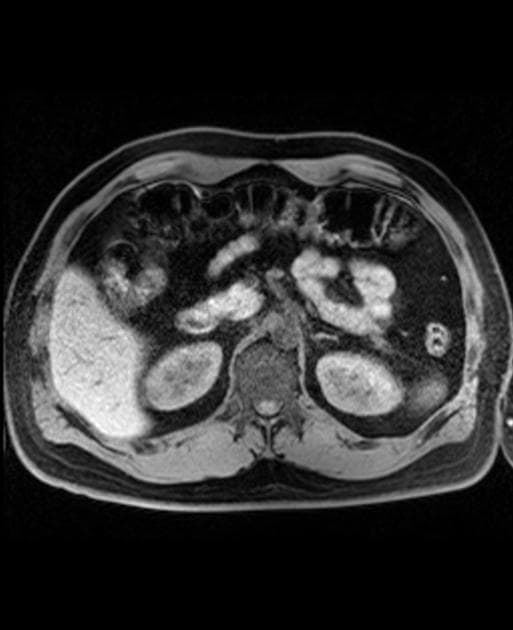

Axial T2

MRCP

Tình trạng sau cắt túi mật, còn lại nang mỏng thành kích thước 7 mm liền kề đầu còn lại của ống túi mật. Không giãn đường mật hay khuyết khuyết tạo hình để gợi ý sỏi trong ống mật.

Có một vài nang gan đơn thuần nhỏ ở các phân đoạn sáu và bảy. Gan có hình ảnh giảm tín hiệu lan tỏa trên T1 out of phase, phù hợp với thoái hóa mỡ (steatosis).

Có hiện tượng tắc nghẽn ống tụy chính tại mức cổ tụy, kèm giãn nhẹ ống chính phía trên (2 mm). Một vùng tròn giới hạn không rõ kích thước khoảng 2 cm ở đầu tụy có tín hiệu T2 tăng nhẹ, nằm gần vị trí tắc ống tụy chính. Tín hiệu hình ảnh khuếch tán (DWI) tăng nhẹ lan tỏa và thể tích tụy tăng nhẹ. Không có dịch quanh tụy hay viêm khu trú.

Adenoma tuyến thượng thận trái ổn định so với CT cách đây 10 năm (không hiển thị). Tuyến thượng thận phải, thận và lách bình thường.